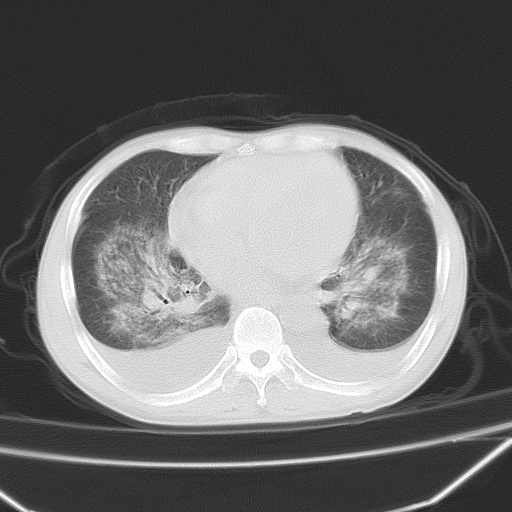

双肺堆成磨玻璃影,双测胸腔积液。考虑:肺水肿、间质性肺炎、真菌感染、ards、hiv感染、肺出血。

双肺野对称性磨玻璃影,分布于内中带,双侧胸水,患者有咯血。

1、间质性肺水肿;2、结合临床病史及实验室检查,考虑为肺出血肾炎综合征。    此病需与间质性炎症、粟粒性肺结核鉴别。

肺出血-肾炎综合征又称good-pasture综合征,属少见病,近几年国内有散在报告。此病原因未明,目前多数学者认为与自身免疫有关,即病人体内存在抗-gbm抗体,而病人肺毛细血管基底膜与肾小球基底膜有交叉反应性抗原,从而引起肺泡毛细血管基底膜和肾小球基底膜病变,导致肺出血及肾炎表现。血清抗-gbm抗体阳性,或组织活检见沿肾小球和肺泡基底膜有igg沉积,为本病的3个诊断依据。临床上有许多疾病同时表现为肺出血和肾炎,如系统性红斑狼疮、韦格肉芽肿和增殖性肾小球肾炎等,但这些疾病都不同时具备上述三方面的条件

双肺野广泛对称性磨玻璃影、实变影,以肺门为中心,主要分布于内中带,符合典型肺泡性肺水肿;伴双侧胸腔少量游离积液。结合患者既往病史且咯血就诊,支持多因素(尿毒症等)所致之肺水肿、肺出血、胸水;影像表现暂不考虑心源性水肿,且症状也不太符。需密切随诊结合临床治疗等进一步明确。